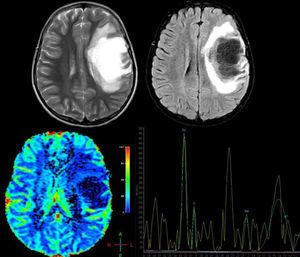

Las técnicas avanzadas de RM son igualmente útiles para el diagnóstico diferencial de estas lesiones. En la espectroscopia por RM se observa disminución del pico de N-acetil aspartato (NAA), lo cual refleja pérdida neuronal, aumento de la intensidad de resonancia del pico de colina (CHO) y lípidos (LIP), consistentes con rotura de la membrana celular y aumento del lactato (LAC), probablemente debido a isquemia secundaria al proceso inflamatorio agudo o producido por los macrófagos activados17,18. No obstante, estos hallazgos son altamente inespecíficos, por lo cual pierden validez y ha llevado a algunos autores a concluir que no es posible diferenciar entre lesiones tumorales y desmielinizantes por medio de la espectroscopia19; sin embargo, una vez el proceso desmielinizante se vuelve crónico, los picos de CHO, LIP, LAC se normalizan y el pico de NAA continua persistentemente bajo, al contrario de lo que sucede en las lesiones tumorales, donde todos los metabolitos continúan alterados, por lo cual algunos autores, en casos donde el diagnóstico no queda claro, recomiendan hacer tratamiento antiinflamatorio y espectroscopia de control para discernir entre ambos procesos17. También fue descrito por Cianfoni et al.20 un interesante hallazgo en la espectroscopia por RM con tiempo de eco corto; se observa un aumento marcado en los picos de glutamato y glutamina, los cuales no son vistos en lesiones tumorales intraaxiales y lo cual se cree sea secundario a reacción astrocitaria (fig. 2).

Paciente femenina de 12 años, sin antecedentes de importancia, quien presentó pérdida aguda de la visión en el ojo derecho (OD) no tratada, 4 meses después presentó afasia y hemiplejía derecha; se solicitó resonancia magnética cerebral (RM), donde se observa: arriba T2 axial y Fluid Attenuation Inversion Recovery (FLAIR) axial. Se observa lesión frontal derecha de comportamiento hiperintenso en T2, hipointenso en T1 y FLAIR con edema vasogénico adyacente y escaso efecto de masa sobre la línea media y el sistema ventricular. Hay imágenes indicativas de estructuras vasculares en el interior de la lesión; abajo, imagen de perfusión cerebral donde se observa disminución de la captación y espectroscopia por RM que demuestra pico de colina a 3,23ppm elevado (que indica un proceso de gliosis y remielinización) y un pico de N-acetil aspartato a 2,05ppm disminuido (que indica daño axonal neuronal) y pico de glutamato y glutamina a 2,4-2,5ppm, hallazgos compatibles con una forma seudotumoral de enfermedad desmielinizante. Se le realizó una biopsia cerebral y los hallazgos histopatológicos son consistentes con LDFS. Se inicia tratamiento con metilprednisolona por 5 días, seguido de un ciclo de plasmaféresis, con excelente respuesta clínica. La paciente recuperó completamente la fuerza del hemicuerpo derecho y el trastorno del lenguaje, permaneció con atrofia óptica del OD. Actualmente, con un seguimiento de un año, sin recaídas.

Otro método de gran utilidad en el diagnóstico diferencial de las lesiones neoplásicas y desmielinizantes son las técnicas de perfusión por RM; en las primeras (tanto gliomas como linfomas del SNC), debido al proceso de angiogénesis el volumen sanguíneo cerebral regional (VSCr) estará marcadamente aumentado y el tiempo de tránsito medio (TTM) se observará disminuido, al contrario de lo observado en las lesiones desmielinizantes, donde no se encuentra aumentado el VSCr, o incluso puede verse disminuido, y el TTM debe mostrarse aumentado14,16 (véase la fig. 2).